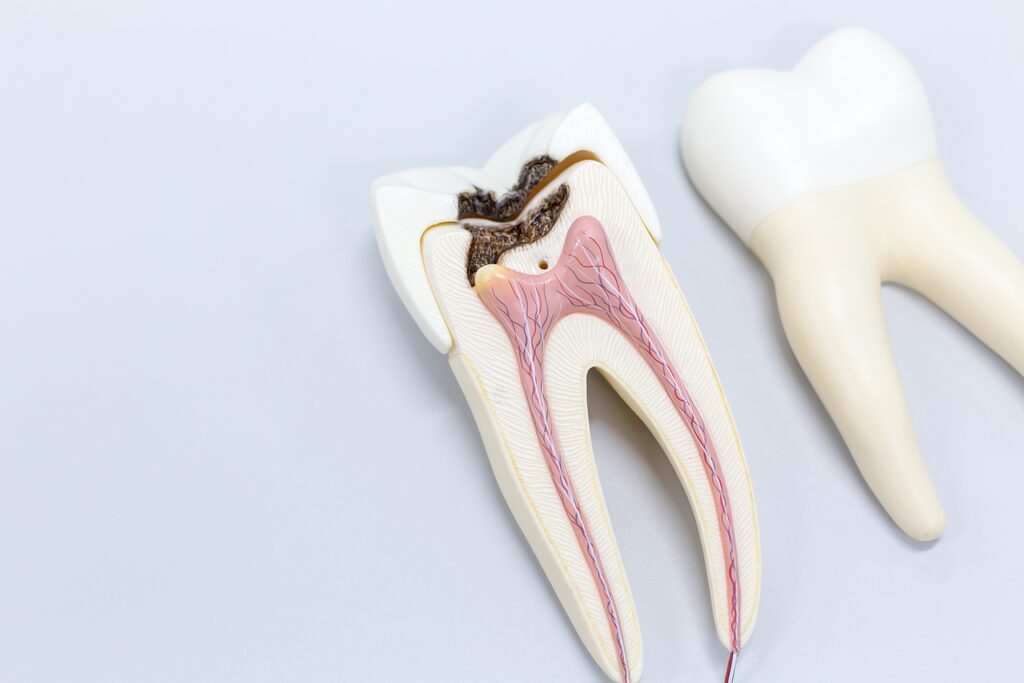

Der Zahnnerv im Inneren des Zahnes kann sich durch Karies, Frakturen, durch Überbelastung oder durch Erkrankung des Zahnhalteapparates entzünden, folgend auch absterben und den Kieferknochen schädigen.

Der Grund: In den engen und kompliziert verzweigten Kanalsystemen der Zahnwurzeln verbleiben bei unzureichender Reinigung Gewebereste sowie Bakterien, die eine Entzündung im Kieferknochen verursachen können.

Das Ziel einer Wurzelbehandlung ist daher eine möglichst gründliche Reinigung des Wurzelkanalsystems. Durch die Entwicklung in der modernen Zahnmedizin ist es mittlerweile möglich, selbst massiv geschädigte Zähne zu retten. Wir verwenden moderne Verfahren, um die Behandlung so angenehm und zügig wie möglich zu gestalten.

Im ersten Schritt wird das infizierte Wurzelkanalsystem mit Hilfe moderner maschineller Aufbereitungsmethoden und desinfizierender Spüllösungen gereinigt. Der entzündete oder abgestorbene Nerv im Inneren des Zahnes wird dabei entfernt. Durch den Einsatz von Ultraschall können auch die schwer zugänglichen Seitenkanäle desinfiziert und rückstandslos gesäubert werden. Eine elektrometrische Längenbestimmung mit einer dreidimensionalen Darstellung misst die genaue Wurzellänge. Denn nur eine Wurzelfüllung, die bis an die Wurzelspitze reicht, gewährleistet einen bakteriendichten Verschluss und verhindert somit die Entstehung neuer Beschwerden. Gelegentlich ist es notwendig, ein Medikament in das Wurzelkanalsystem des Zahnes einzubringen, um die Bakterien zu eliminieren. Am Ende der Behandlung wird das Kanalsystem mit einer Füllung und ggf. später mit einer Krone fest verschlossen, die den Zahn bei Kaubelastung optimal stabilisieren kann.